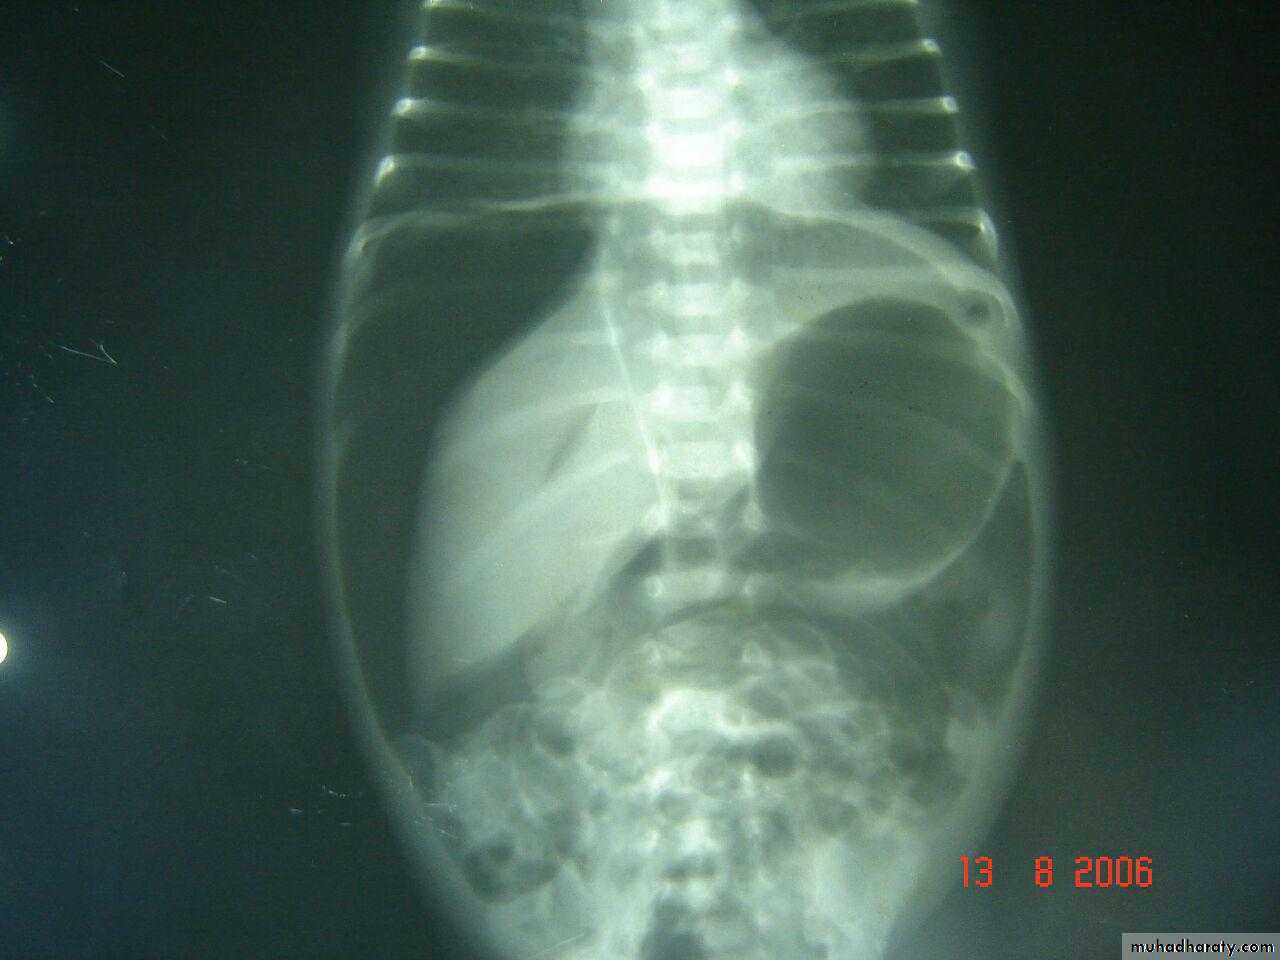

Diaphragmatic hernia

Rt. Diaphragmatic hernia or diaphragmatic eventration

Rx >> endotracheal tube and o2 and NG tubeDiaphramatic hernea and endotracheal tube

Rt. Diaphragmatic hernia (rare) + pneumothorax in lt. due to lung hypoplasia